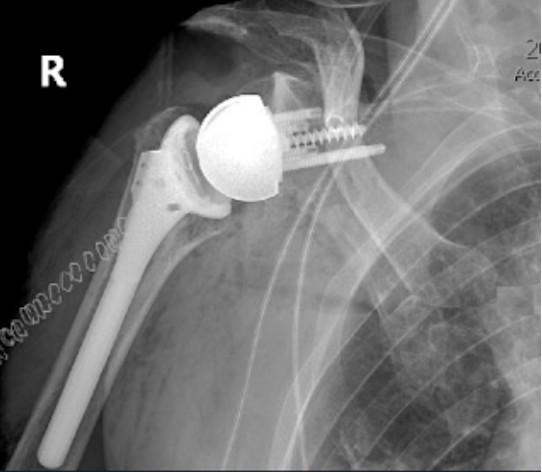

Four recently published articles provide important new information about the ream and run procedure for active patients with shoulder arthritis Those readers interested in learning more can access a discussion of these new articles here: shoulderarthritis.blogspot.com/2026/03/cocr-r…